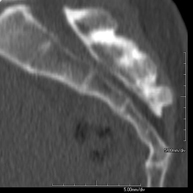

- TC Columna lumbar

Prueba radiológica que consiste en obtener imágenes de las vértebras lumbares de alta definición anatómica mediante el empleo de un equipo de TC (Tomografía Computarizada). Indicaciones: dolor lumbar sin/con irradiación a piernas, dificultad para caminar, traumatismo.